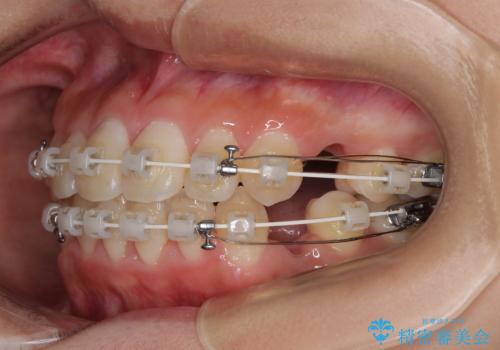

急速拡大装置 狭い骨幅を拡大した上で、口元の突出感を改善する抜歯矯正治療

単純に上下左右の第一小臼歯4本を抜歯して口元の突出感を改善することも考えられましたが、上顎骨よりも下顎骨の幅が広いため、より良い咬み合わせを達成することを目的として、急速拡大装置を用いて上顎骨を拡大することとしました。

歯列矯正では基本的に骨格を改善することはできませんが、急速拡大装置(MARPE)を使用することで上顎骨を側方に拡大させることができ、咬合状態を大きく改善することができます。